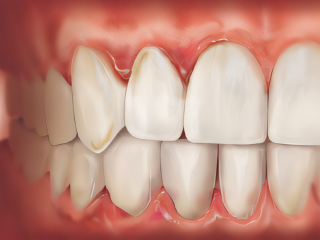

greffe-gingivale

Chirurgie Muco-Gingivale

Renforcer et harmoniser le cadre de votre sourire. Il se peut que votre gencive soit fine, qu’elle se rétracte sans infection bactérienne sous-jacente.

Au-delà de l’aspect esthétique, la chirurgie muco-gingivale vise à corriger les anomalies de la gencive et à protéger vos dents sur le long terme. Qu’il s’agisse de traiter une récession gingivale (dent qui se déchausse) par une greffe ou de redessiner les contours d’un sourire, notre objectif est de restaurer l’épaisseur et la hauteur de la gencive.

Ces interventions permettent de :

• Réduire la sensibilité dentaire au chaud et au froid.

• Protéger la racine contre les agressions et les caries.

Améliorer l’esthétique de votre sourire en retrouvant une ligne de gencive harmonieuse.